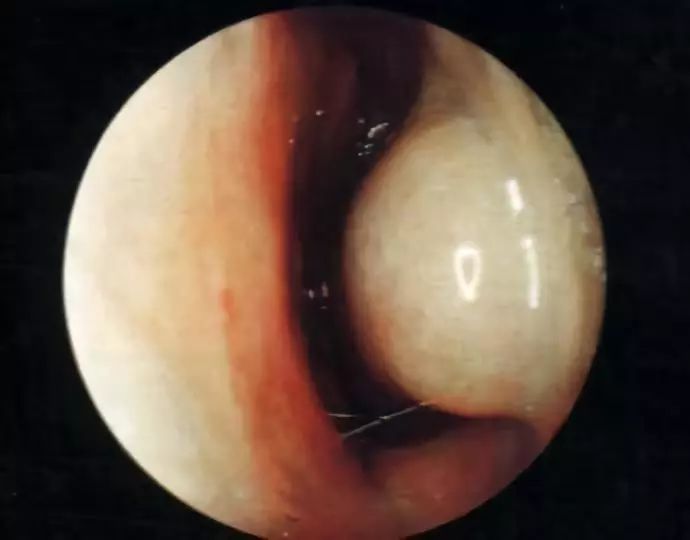

鼻甲肿大、腺体分泌亢进